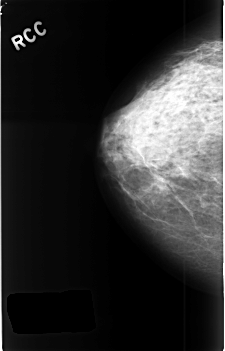

ics_version 1.0 filename C-0440-1 DATE_OF_STUDY 21 7 1995 PATIENT_AGE 48 FILM FILM_TYPE REGULAR DENSITY 3 DATE_DIGITIZED 23 11 1998 DIGITIZER LUMISYS LASER SEQUENCE LEFT_CC LINES 4584 PIXELS_PER_LINE 2912 BITS_PER_PIXEL 12 RESOLUTION 50 NON_OVERLAY LEFT_MLO LINES 4592 PIXELS_PER_LINE 2880 BITS_PER_PIXEL 12 RESOLUTION 50 OVERLAY RIGHT_CC LINES 4552 PIXELS_PER_LINE 2920 BITS_PER_PIXEL 12 RESOLUTION 50 NON_OVERLAY RIGHT_MLO LINES 4584 PIXELS_PER_LINE 2888 BITS_PER_PIXEL 12 RESOLUTION 50 NON_OVERLAY |